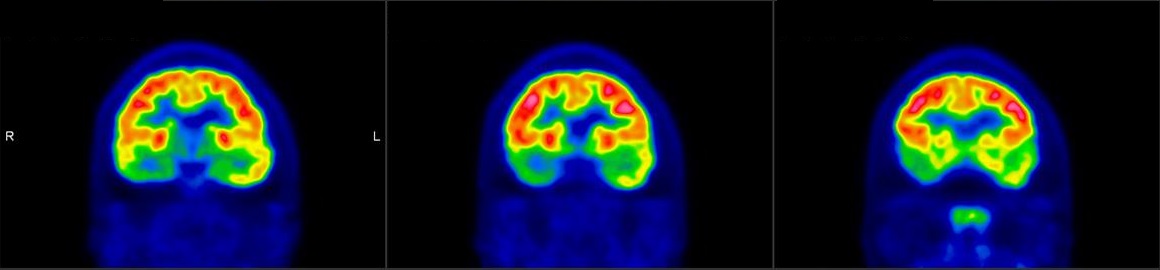

脑神经科

![]() [C-11] PIB |

![]() [C-11] Raclopride |

![]() [F-18] DOPA |